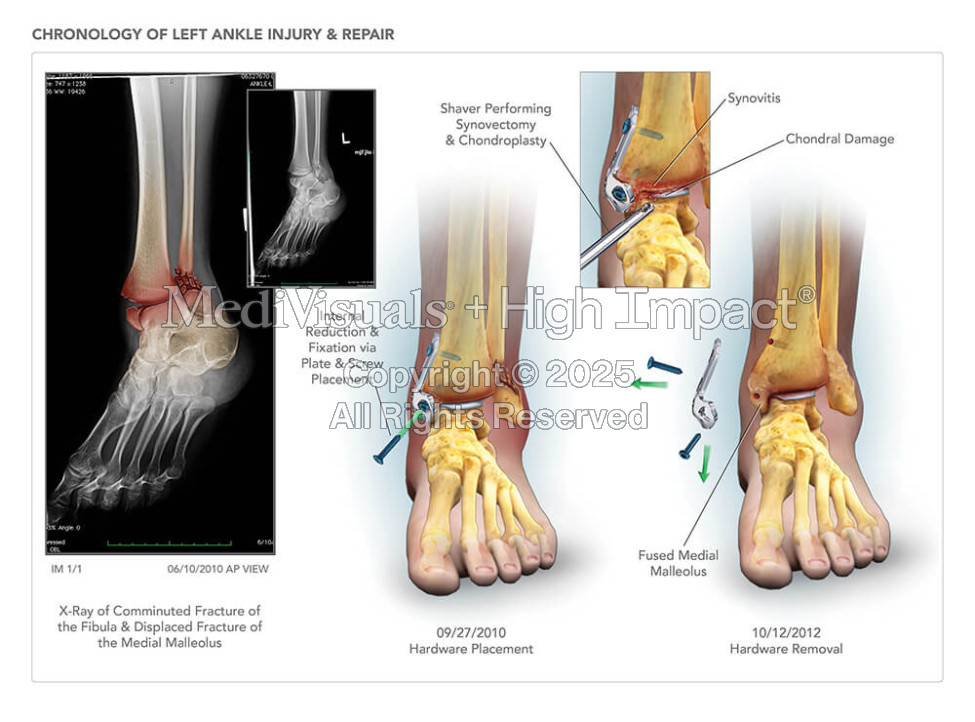

Chronology of Ankle Injury & Repair

Available in high resolution JPEG or PDF formats, 8x10 print, or laminated foam core exhibit board (24x46, 30x40 or 36x48).